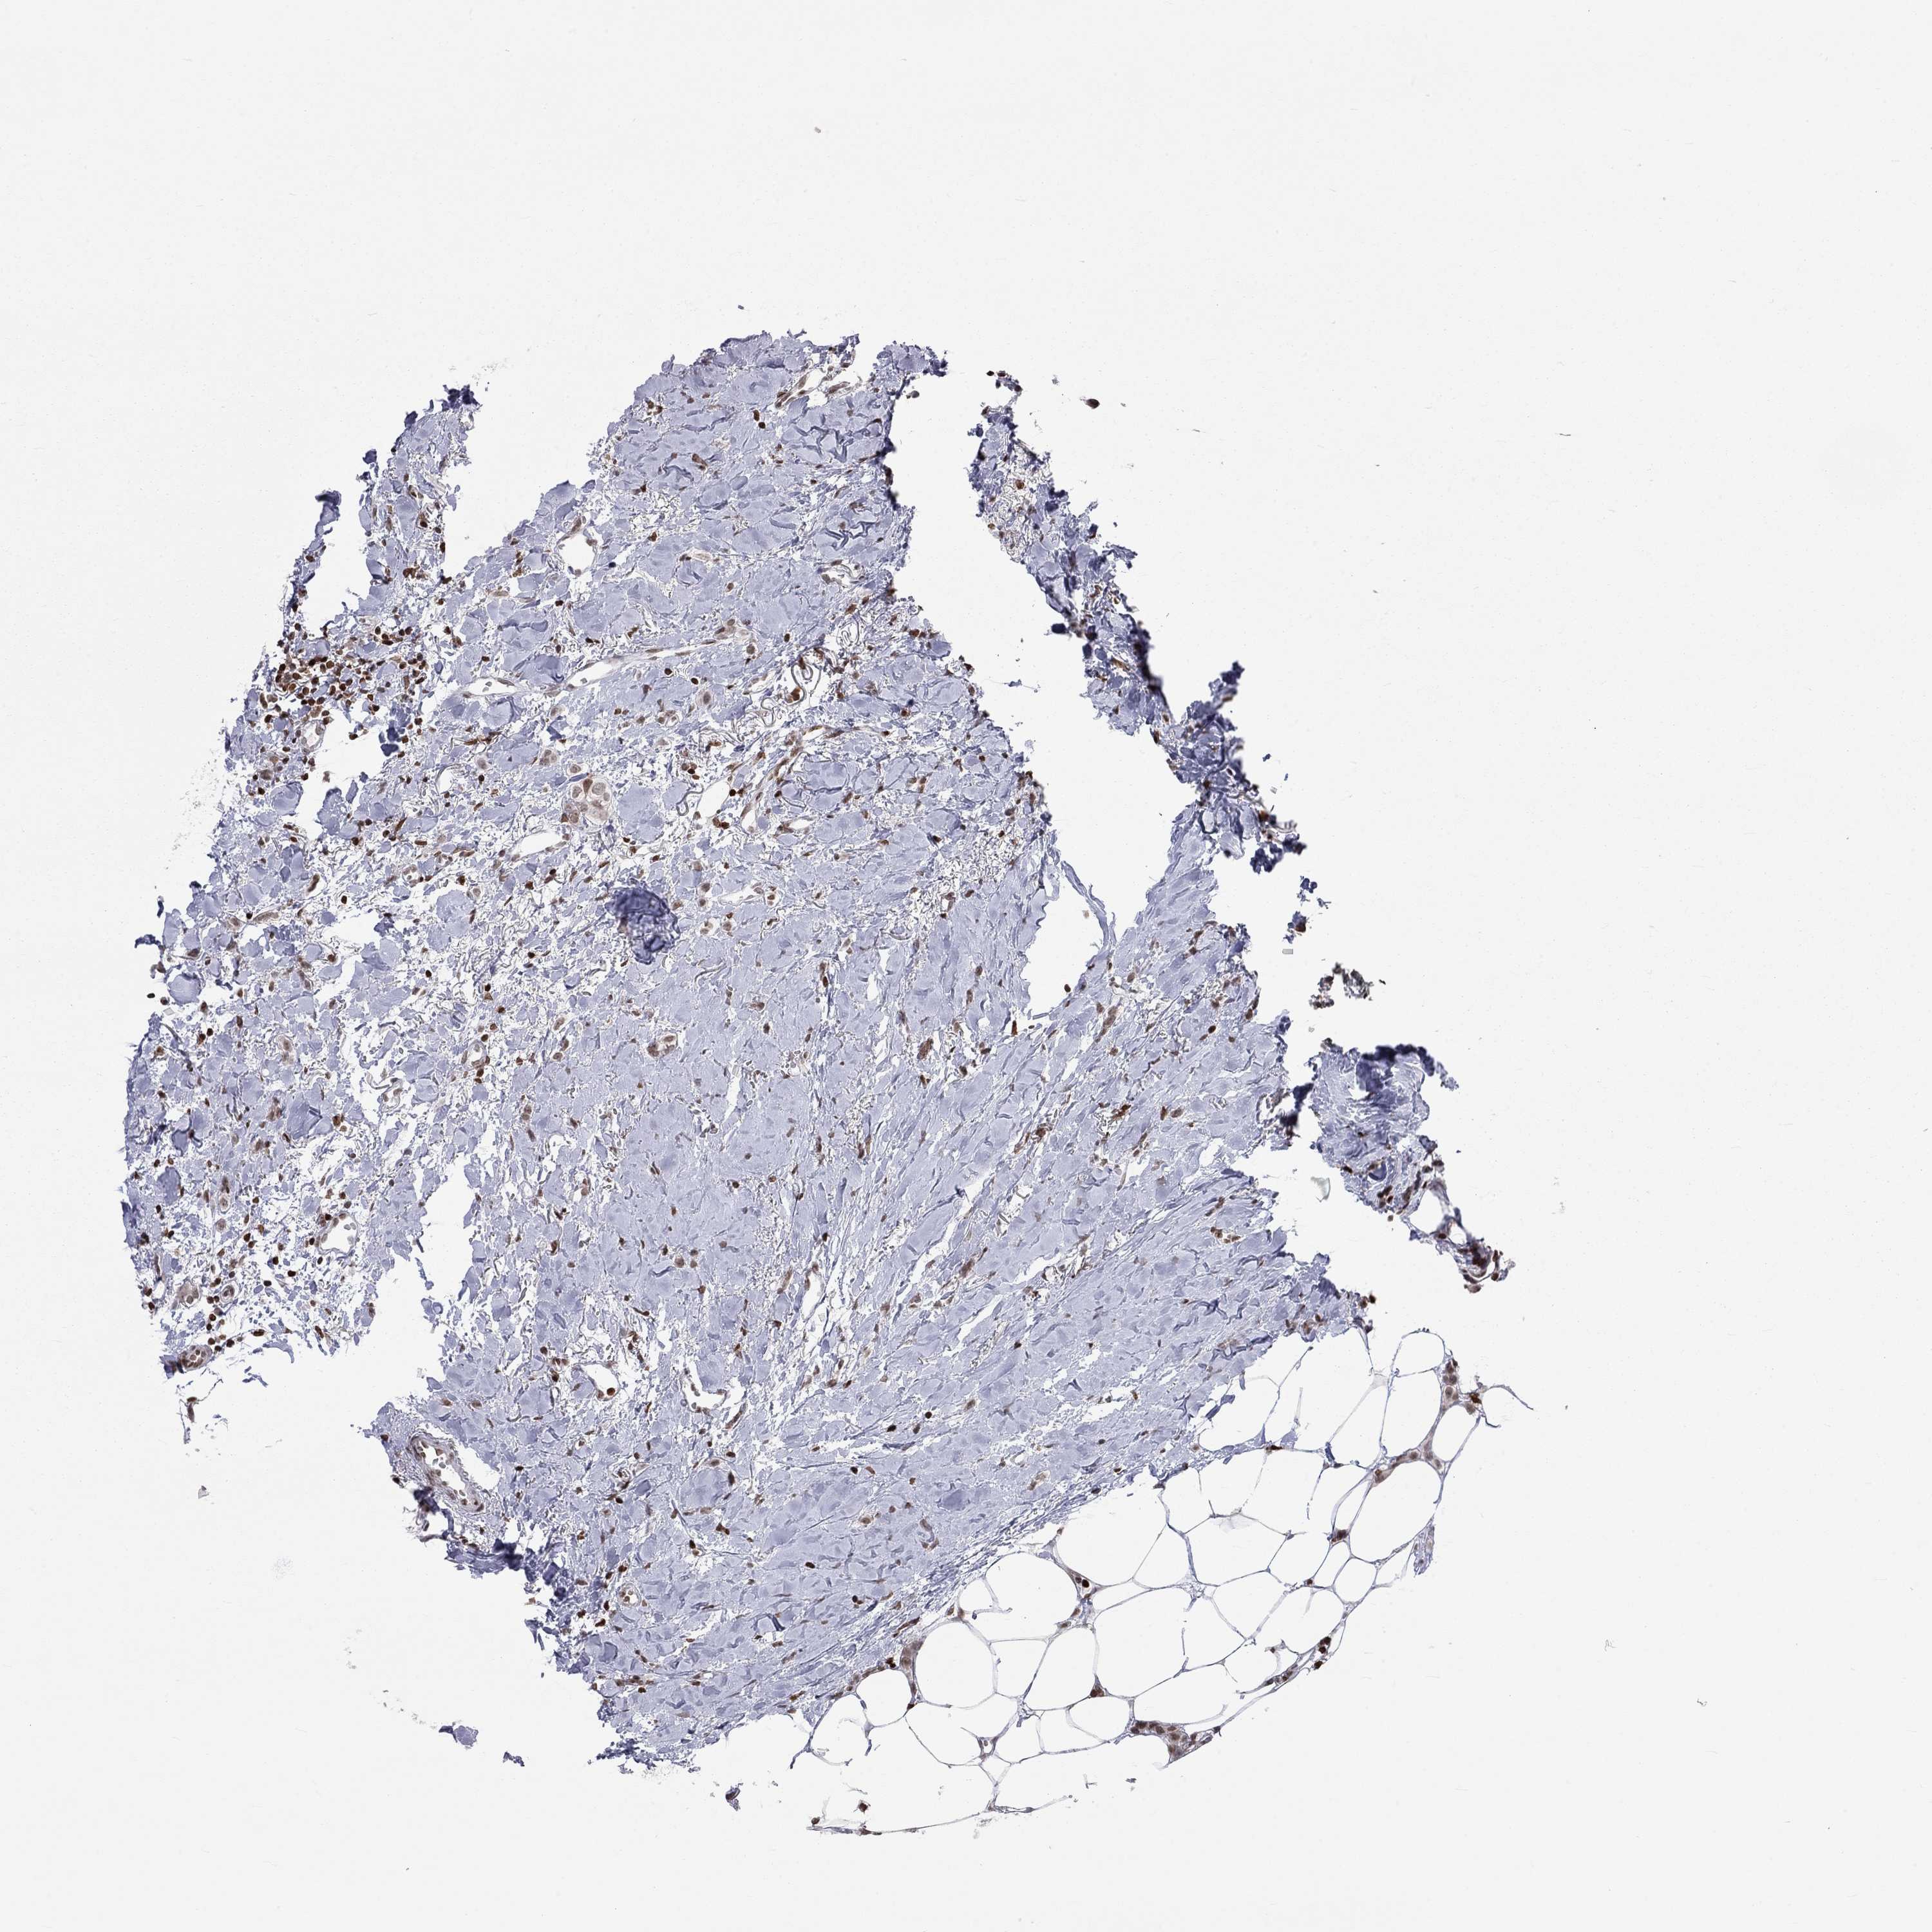

H2AX

• H2AX